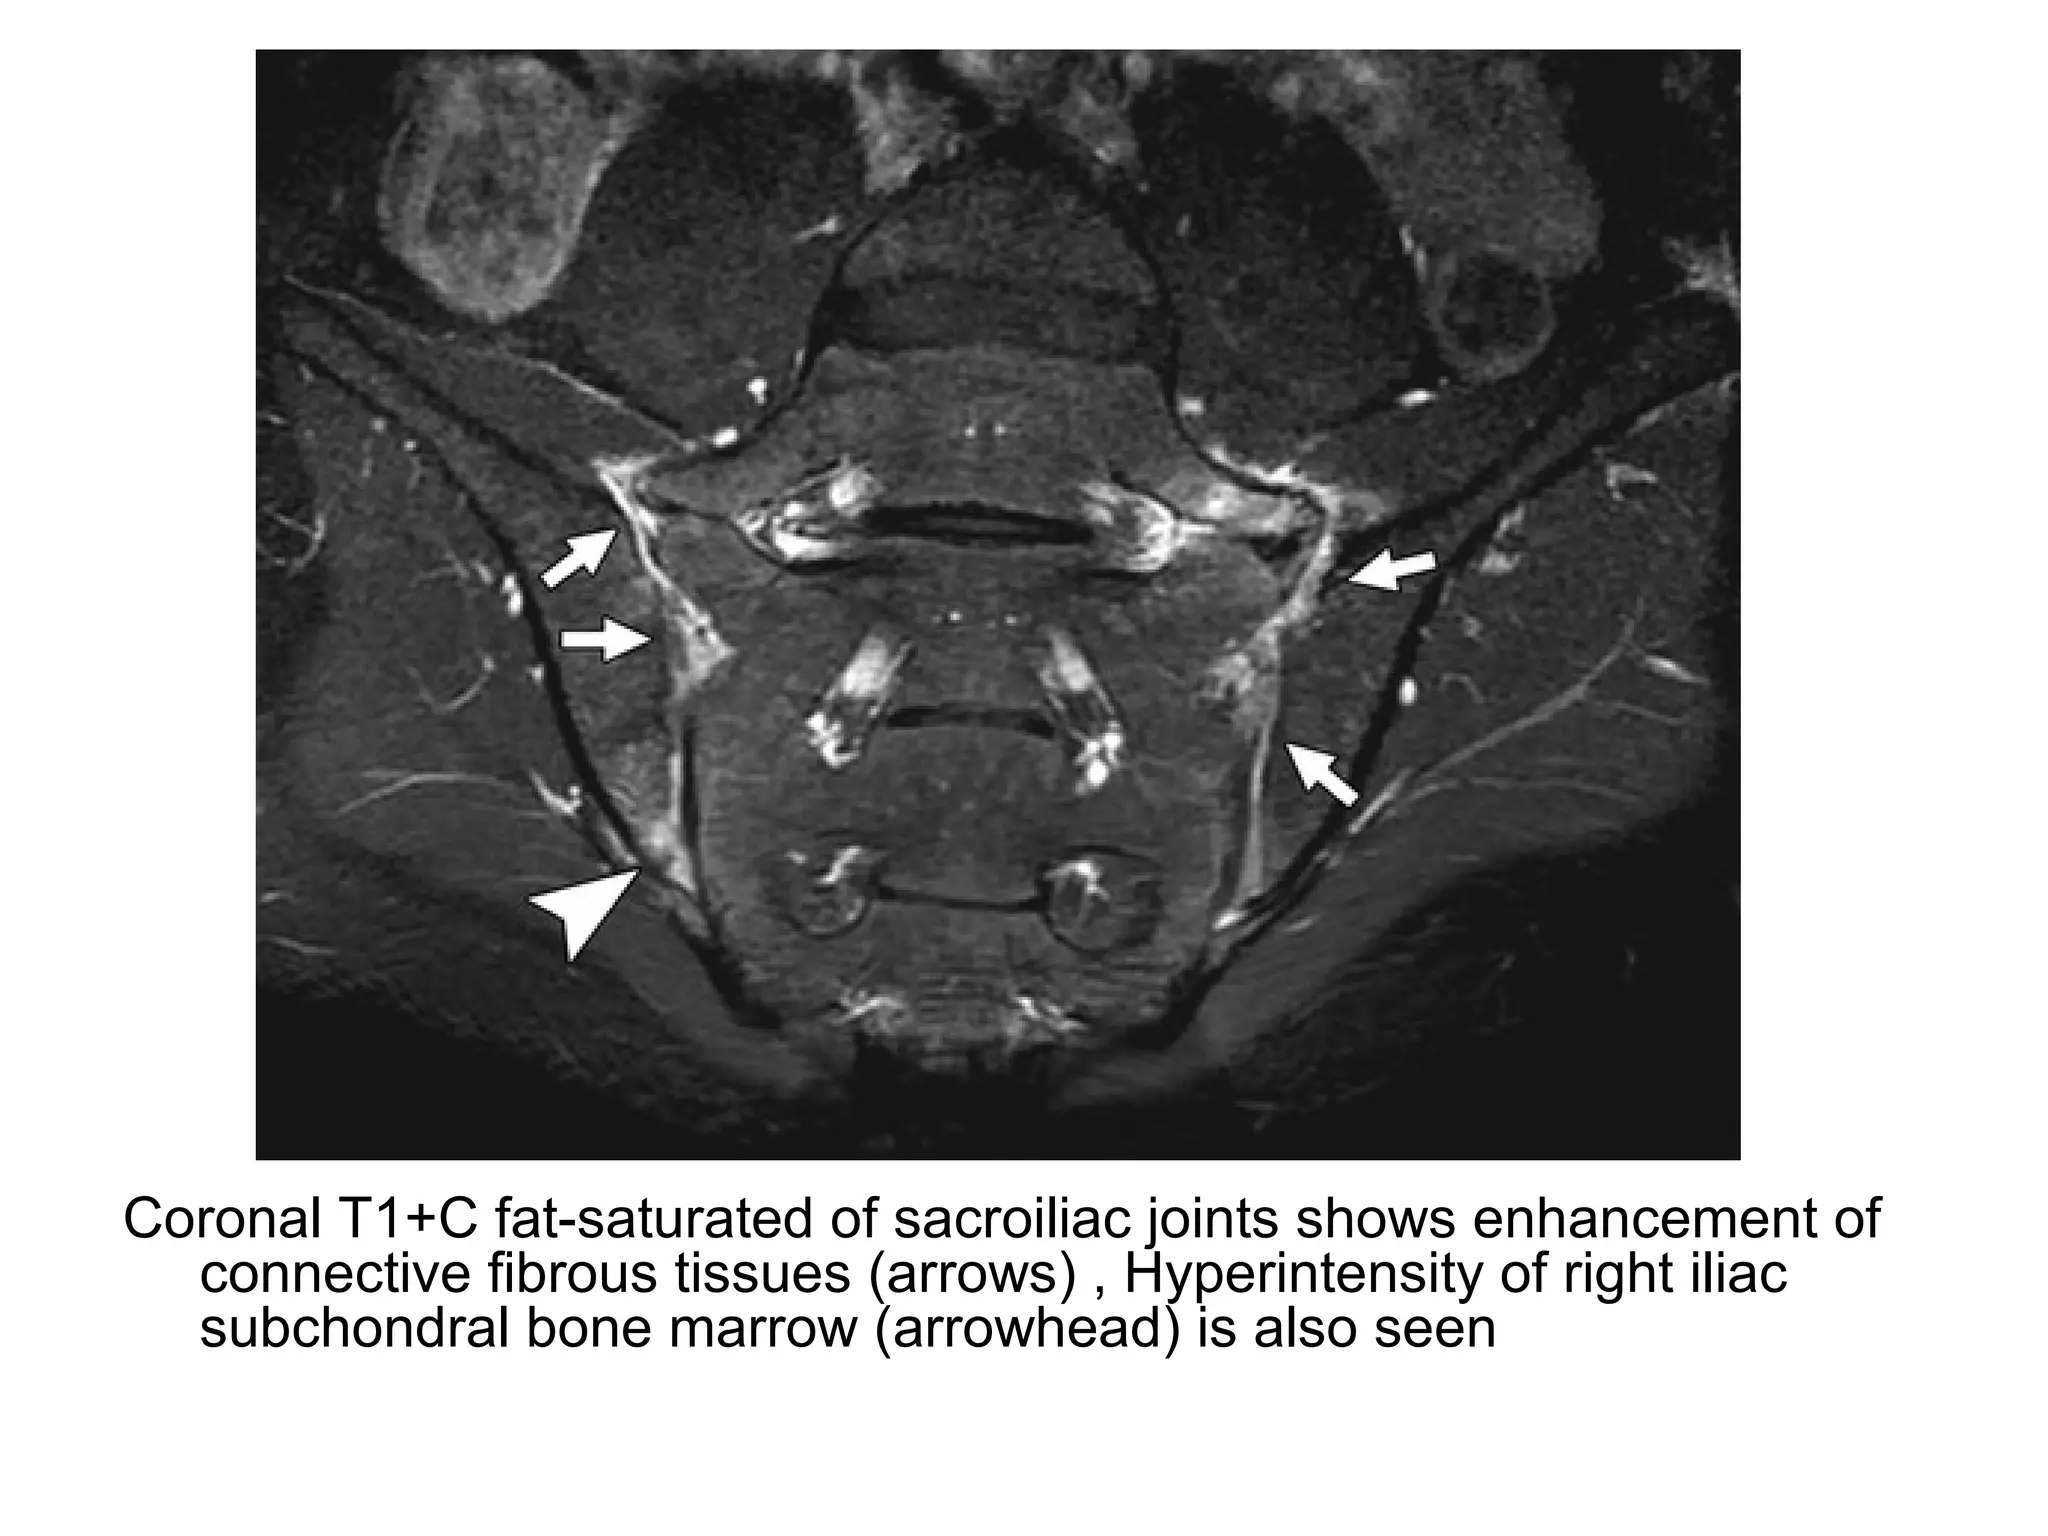

Coronal T1+C fat-saturated of sacroiliac joints shows enhancement of

connective fibrous tissues (arrows) , Hyperintensity of right iliac

subchondral bone marrow (arrowhead) is also seen